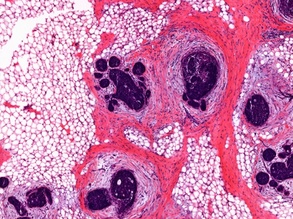

Fat Checking